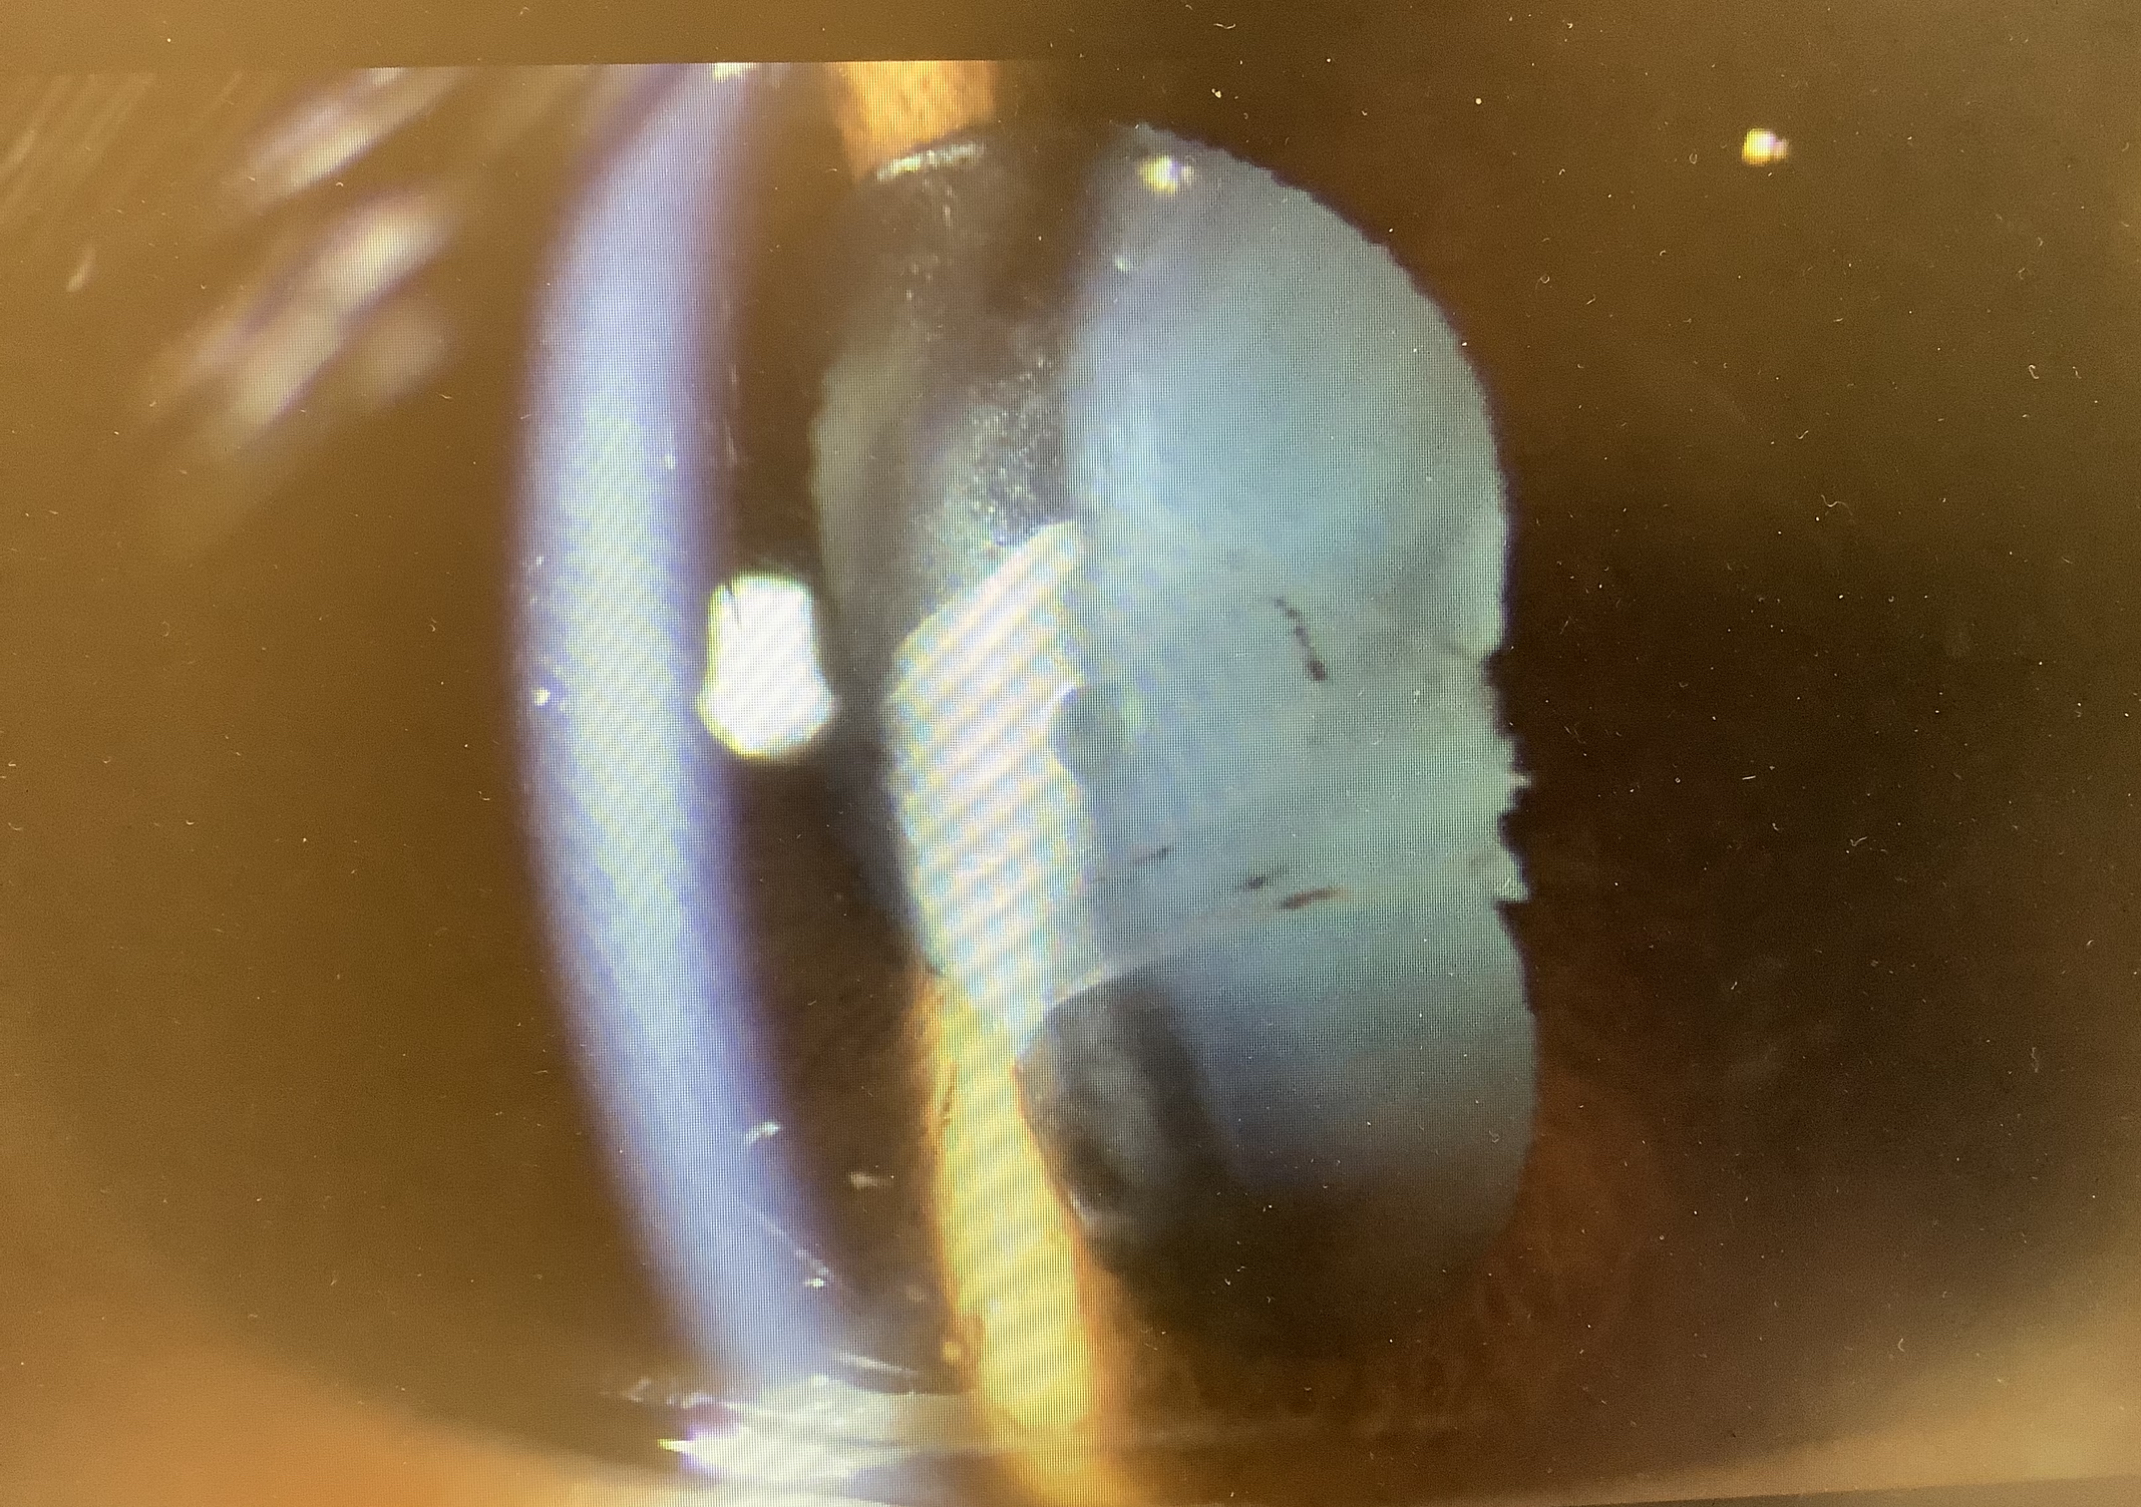

先週の金曜日にICLの手術を受けていただいた30代の男性の方の定期受診がありましたが、『日曜日くらいから右眼が白く濁って見えにくかった。今日は少しいいけど。』という症状があり、術翌日の視力1.2から今日は0.3まで低下し、眼の中を見ると、レンズの表面に白い膜が張っており、眼内の強い炎症が起こっている状況でした。術後の炎症は“眼内炎”といわれ、細菌感染による“細菌性(感染性)眼内炎”と感染以外の原因による“無菌性眼内炎”があります。一般的に眼内炎というと、細菌性の眼内炎のことを指すことが多いかと思いますが、細菌性眼内炎は手術の際に目の中に入った細菌が術後、徐々に増えてくるので、術直後から数日はまだ細菌が多くないので、症状としては問題なく(状態としては問題がありますが、、、)、術後3〜4日くらいで視力低下、眼の痛み、充血、眼脂などの症状が出るのが典型とされています。一方、無菌性眼内炎は、手術の際に使う薬剤や器具に付着する不純物が眼の中に入り、それに対する拒絶反応のような病態なので、比較的、術後すぐに炎症が強く出るとされています。細菌性眼内炎は進行すると、炎症が硝子体の方まで波及し、網膜の血管が細菌の毒素によって障害を受け、適切な処置を行わないと重篤な視力障害を残してしまうこともあります。無菌性の場合、あくまで主体は炎症反応なので、炎症を抑えるステロイドがよく効き、硝子体まで炎症が拡がることは基本的にないとされています。

今回の患者さまの場合、術後2日目から症状が出ていること、ステロイドの点眼で改善傾向なこと、眼脂・充血・眼痛といった細菌性眼内炎にみられるとされる症状が乏しいことから、おそらくは無菌性の眼内炎と思われました。なので、保存的治療で見ることも可能かもしれないと思われましたが、細菌性眼内炎の可能性もゼロではありませんし、無菌性眼内炎を起こす物質がまだ眼の中に留まっていることは十分考えられ、早く炎症を抑えるためにも、眼の中を洗う処置(前房洗浄)を緊急でさせていただきました。患者さまには負担になってしまい、申し訳ありませんでしたが、処置自体は新たにキズを作る訳ではなく、前回のキズをもう一度開け、眼の中の前のスペース(前房)を3分ほど洗わせていただきました。ICLの場合、レンズの裏面は中央のホール越しに洗わなければならず、白内障の手術に比べると、薬剤や異物(レンズを入れるインジェクターのコーティングなど)が眼の中に残りやすいのがあるのかと思います。